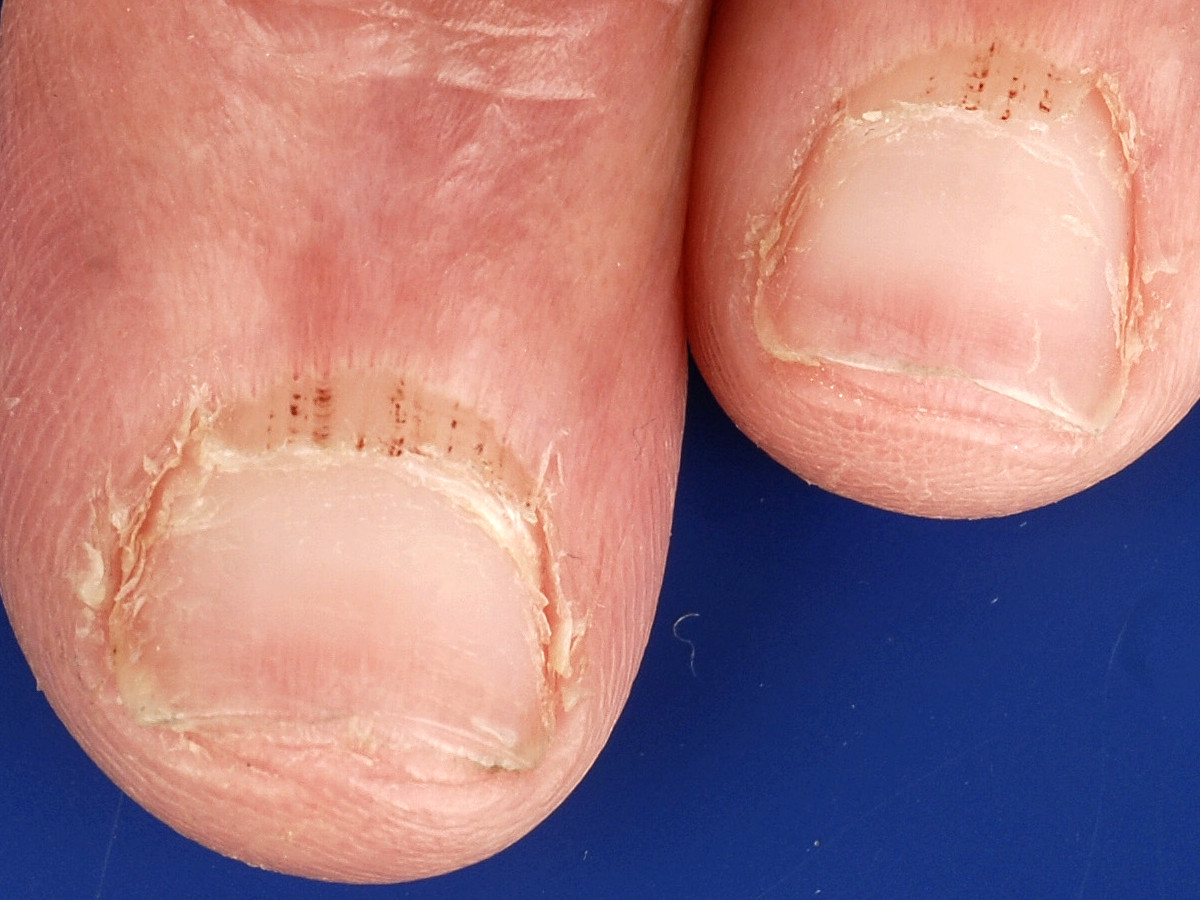

Splinterbloedingen in de nagel (splinter haemorrhages, hemorrhages, splinter bleeding) zijn kleine bloedstolsels of erytrocyten extravasaties onder de nagel, meestal langwerpig. Ze kunnen zowel proximaal als distaal voorkomen. Splinterbloedingen kunnen voorkomen bij een bacteriƫle endocarditis en bij vasculitis, maar ze kunnen ook spontaan ontstaan zonder duidelijke oorzaak, of door trauma of antistolling (zie tabel). Bij endocarditis zijn er soms ook rode niet wegdrukbare laesies in de handpalmen of voetzolen (Janeway lesions genoemd). Ook in de nagelriem kunnen splinterbloedingen voorkomen door beschadigingen van de capillairen ter plaatse, vooral bij auto-immuunziekten. Dit kan worden beoordeeld met de dermatoscoop (capillairoscopie).

Splinterbloedingen Splinterbloedingen Splinterbloedingen

splinterbloedingen splinterbloedingen nagelriem bloedingen